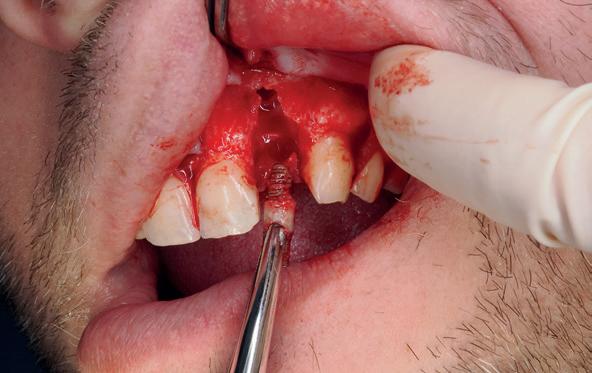

Implantologische behandelingen in het esthetische front vragen meer dan technische vaardigheid alleen. Ze vragen om overzicht, timing, vertrouwen en een team dat als vanzelf samenwerkt onder druk. Juist bij complexe casussen, waarin angst, infectie en hoge esthetische verwachtingen samenkomen, wordt zichtbaar hoe bepalend de rol van de tandartsassistent is.

Deze casus beschrijft een uitgebreide immediate implantaatbehandeling bij een patiënt die door meerdere collega’s werd geweigerd. Niet omdat de mogelijkheden ontbraken, maar omdat de complexiteit vroeg om een perfect afgestemde samenwerking. Het verhaal laat zien hoe de assistent in zo’n traject veel meer is dan een uitvoerende kracht of “mal”, maar een dynamische surgical guide die het proces mede stuurt, bewaakt en mogelijk maakt.De patiënt: wanneer alles samenkomt

Na het klinische onderzoek volgde het röntgenologisch traject. De CBCT liet precies zien wat we al vreesden: een front waarin het bot onregelmatig was, duidelijke radiolucenties rond de pijlers en een infectiegebied dat zich onder vrijwel de gehele brug had verspreid. Tegelijkertijd was er ook potentie. Net voldoende botstructuur om immediate implantaatplaatsing te overwegen, mits alles perfect gepland zou worden.